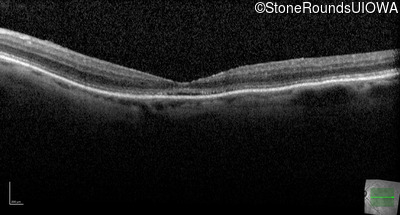

The clinical features favoring the diagnosis of RP1L1-associated occult macular dystrophy include: reduced acuity with a near-normal ophthalmoscopic appearance, a history of normal acuity in childhood; and, a "moth-eaten" appearance of the macular ellipsoid zone on OCT.

Age at visit: 77 years